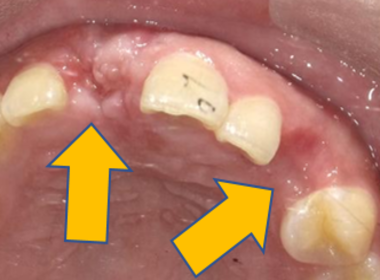

| 0112 #15 右上第二小臼齒 |

![]() |